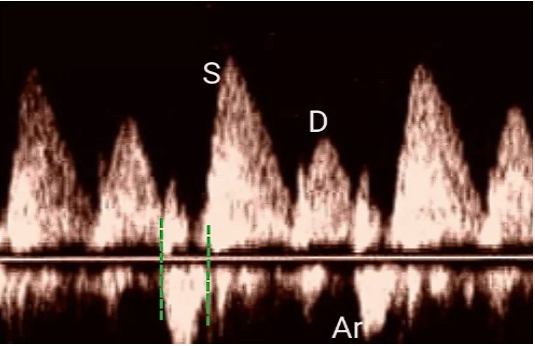

(7)肺静脉血流频谱:在心尖四腔心切面,取样容积2 mm,在右上肺静脉内深约0.5 cm处获取血流频谱(PW)。其参考波形如图28所示。

图片

图28. 肺静脉血流频谱PW示意图

包括收缩期顺行波峰S峰,舒张早期顺行波峰D峰,舒张晚期逆行波峰Ar。一般来说,对于40岁以上成人,肺静脉血流频谱的S/D大于1。

在左室松弛性降低阶段,S/D大于1且Ar大于35 cm/s;在假性正常阶段,S/D小于1,Ar升高或不变;在限制性充盈阶段,S/D进一步降低,Ar升高超过35 cm/s,且Ar时间减去PW下二尖瓣血流频谱A峰时间的差值大于30ms。